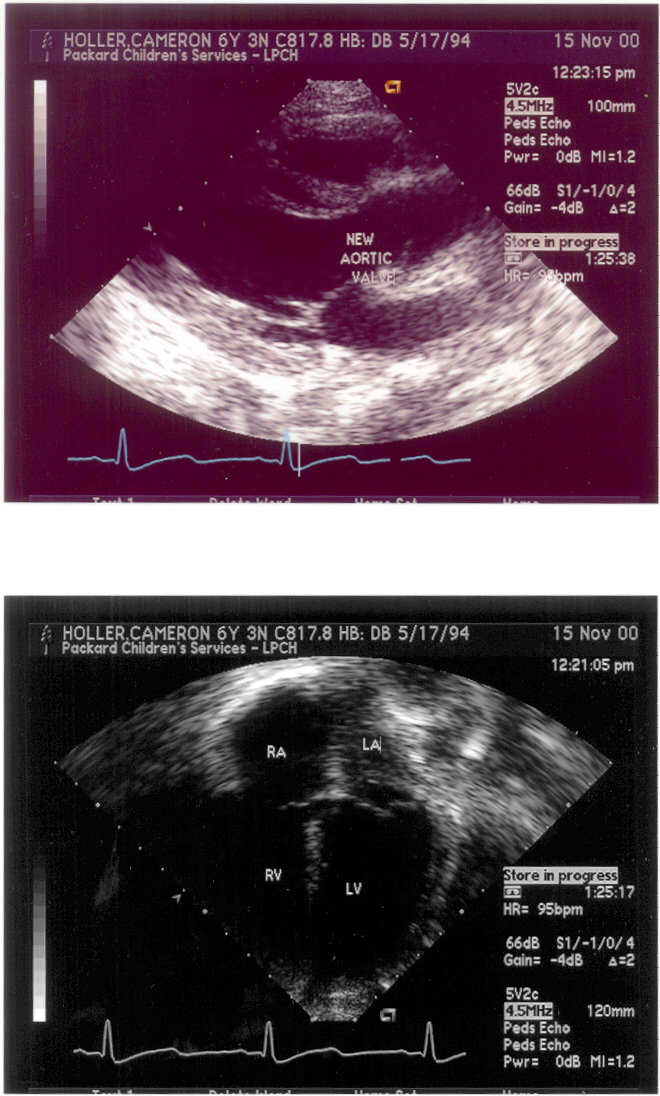

Some Post Surgery 11/13/00, pictures.

Dr. Michael Black and Team at Lucile Packard Children's Hospital performed this most successful surgery. Dr. Richard Greene at the Palo Alto Medical Foundation first discovered the condition 6 years ago and guided us through the difficult decision making process up to the surgery. We cannot describe our appreciation for what these doctors have done for Cameron and our family.